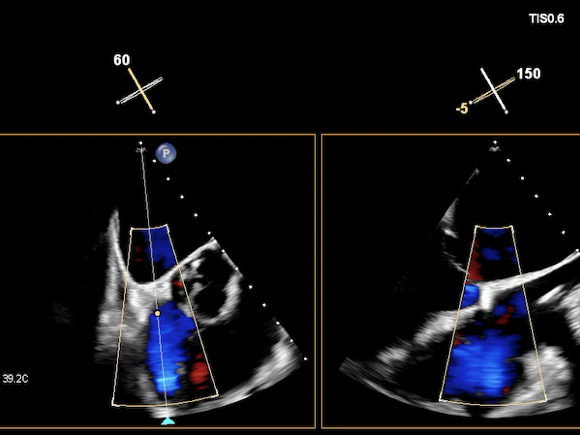

术前超声

重度三尖瓣反流(4+)。